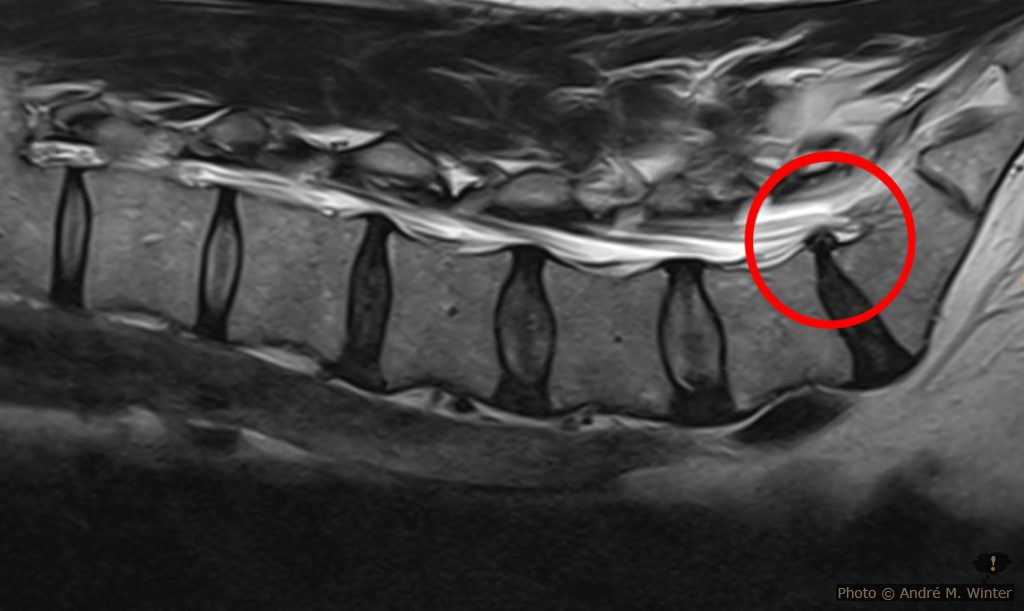

Die Wirbelsäule wird gleich am Tag drauf, Dienstag, durch das MRT gejagt. Volle 50 Minuten in der dröhnenden Röhre sind echt nichts für schwache Nerven. Dank Privatklink ist der neuerliche Neurologie-Termin gleich am Mittwoch. Wirbelsäule altersgerecht. Ein kleiner Bandscheibenvorfall zwischen den vorletzten und vorvorletzten Lendenwirbeln, genau dort wo dies an keinen Nerv drücken kann, also irrelevant. Das sind halt so die Nebenbefunde. Wann hat man schon mal ein Wirbelsäulen-MRT in der Hand? Fazit: Neurologische Ursachen sind derzeit zur Gänze ausgeschlossen. Der Neurologe ist natürlich auch Arzt und schliesst Gefässkrankheiten aus, dies auch in Bezug auf das Auftreten der Schmerzen, die nun permanent sind. Das sah damals auch die Orthopädin so. Der Neurologe meint zu recht, dass der Ausschluss von Nervenkrankheiten sehr gut ist. Er entlässt mich jedoch mit Bedauern weil er mir nicht helfen konnte.